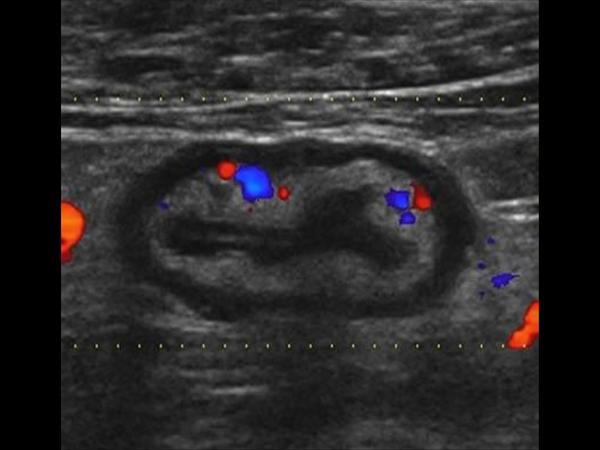

Viêm đại tràng

Viêm đại tràng - Ảnh 2

» Thông tin: Nam giới – 41 tuổi.

» Lâm sàng: Đau hạ vị.